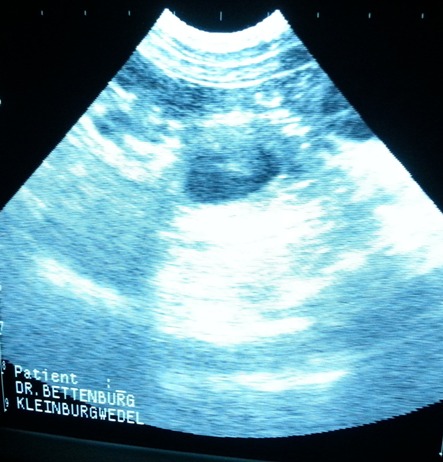

-26.10.2012 heute war ich mit Toffee beim Ultraschall..... Sie ist Trächtig !!!! ich freu mich riesig und bin schon sehr gespannt auf den Wurf

erstes Babyfoto